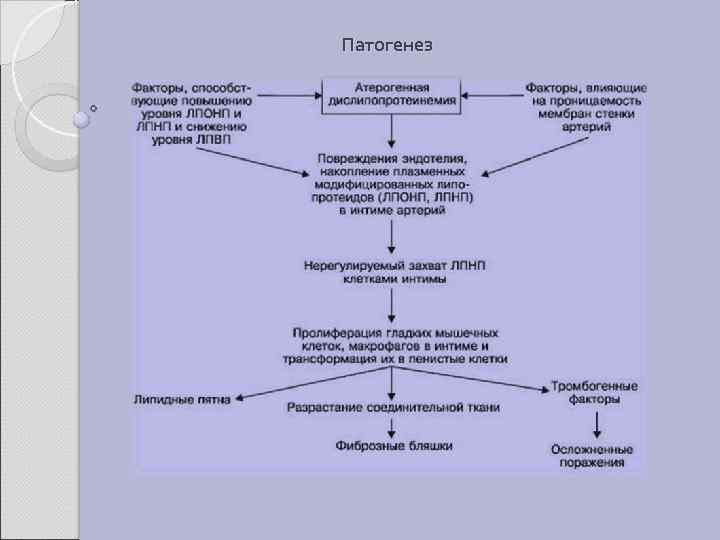

Патогенез

2. 1 АТЕРОСКЛЕРОЗ Атеросклероз — хроническое заболевание эластического и мышечно-эластического типа, возникающее вследствие нарушения липидного обмена и сопровождающееся отложением холестерина и некоторых фракций липопротеидов в интиме сосудов. Отложения формируются в виде атероматозных бляшек. Последующее разрастание в них соединительной ткани (склероз), и кальциноз стенки сосуда приводят к деформации и сужению просвета вплоть до облитерации (закупорки). Этиология На данный момент единой теории возникновения данного заболевания нет. Выдвигаются следующие варианты, а также их сочетания: • теория липопротеидной инфильтрации — первично накопление липопротеидов в сосудистой стенке, • теория дисфункции эндотелия — первично нарушение защитных свойств эндотелия и его медиаторов, • аутоиммунная — первично нарушение функции макрофагов и лейкоцитов, инфильтрация ими сосудистой стенки, • моноклональная — первично возникновение патологического клона гладкомышечных клеток, • вирусная — первично вирусное повреждение эндотелия (герпес, цитомегаловирус и др. ), • перекисная — первично нарушение антиоксидантной системы, • генетическая — первичен наследственный дефект сосудистой стенки, • хламидиозная — первичное поражение сосудистой стенки хламидиями, в основном, Chlamydiapneumoniae. • гормональная — возрастное повышение уровня гонадотропных и адренокортикотропных гормонов приводит к повышенному синтезу строительного материала для гормонов-холестерина.

Клиника Клинические проявления часто не соответствуют морфологии. При патологоанатомическом вскрытии обширное и выраженное атеросклеротическое поражение сосудов может оказаться находкой. И наоборот, клиника ишемии органа может появляться при умеренной облитерации просвета сосуда. Характерно преимущественное поражение определенных артериальных бассейнов. От этого зависит и клиническая картина заболевания. Поражение коронарных артерий постепенно приводит к коронарной недостаточности, проявляющейся ишемической болезнью сердца. Заинтересованность церебральных артерий вызывает либо преходящую ишемию мозга либо инсульты. Поражение артерий конечностей — причина перемежающейся хромоты и сухой гангрены. Атеросклероз брыжеечных артерий ведет к ишемии и инфаркту кишечника (мезентериальный тромбоз). Также возможно поражение почечных артерий с формированием почки Голдблатта. Даже в пределах отдельных артериальных бассейнов характерны очаговые поражения — с вовлечением типичных участков и сохранностью соседних. Так, в сосудах сердца окклюзия наиболее часто возникает в проксимальном отделе передней межжелудочковой ветви левой коронарной артерии. Другая типичная локализация — проксимальный отдел почечной артерии и бифуркация сонной артерии. Некоторые артерии, например внутренняя грудная, поражаются редко, несмотря на близость к коронарным артериям и по расположению, и по строению. Атеросклеретические бляшки часто возникают в бифуркации артерий — там, где кровоток неравномерен; иными словами, в расположении бляшек играет роль локальная гемодинамика (см. патогенез).